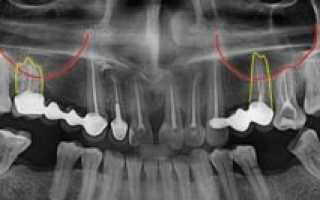

На фото: корни зубов у дна верхнечелюстной пазухи

- Близкое расположение корней моляров и премоляров. В некоторых случаях толщина костного слоя между зубными корнями и дном гайморовой пазухи может быть сравнительно большой — до 1 см, но у некоторых людей костная граница между этими образованиями совсем тонкая — не более 1 мм.

- Иногда корни первого и второго моляров располагаются в самой полости пазухи, отделяясь от нее всего лишь слоем слизистой оболочки.

На фото: зубной корень находится в близости от дна гайморовой пазухи, что увеличивает вероятность перфорации при удалении

Такое расположение гайморовых пазух представляет опасность при стоматологических манипуляциях с верхними зубами. У каждого человека длина их корней может быть различна. У одних людей корни не доходят до дна гайморовой пазухи на 1 сантиметр, а у других пронизывают весь альвеолярный отросток и заканчиваются в полости, даже приподнимая слизистую оболочку.